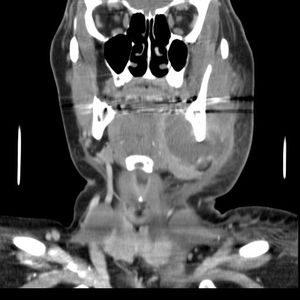

치아 농양을 치료하지 않고 방치하면 뼈를 관통하고 연조직으로 확장될 정도로 커져 골수염 및 봉와직염으로 진행될 수 있다. 거기에서 감염은 최소 저항 경로를 따라 내부 또는 외부로 퍼질 수 있다. 감염 경로는 감염된 치아의 위치, 뼈, 근육 및 근막 부착 부위의 두께와 같은 요인의 영향을 받는다.

내부 배농은 성장하는 감염이 감염 주변 조직 내에서 공간을 만들기 때문에 더 우려된다. 즉시 입원이 필요한 심각한 합병증으로는 성장하는 감염과 봉와직염의 조합인 루트비히 협심증이 있으며, 이는 극단적인 경우 기도를 닫아 질식을 유발할 수 있다. 또한 감염은 조직 공간을 따라 종격동으로 퍼져 심장과 같은 생명 유지 기관에 심각한 영향을 미칠 수 있다. 또 다른 합병증은 일반적으로 위쪽 치아에서 발생하며, 패혈증이 경로를 통해 이동하여 심내막염, 뇌 농양 (극히 드물게), 또는 수막염 (또한 드물게)으로 이어질 수 있는 위험이 있다.